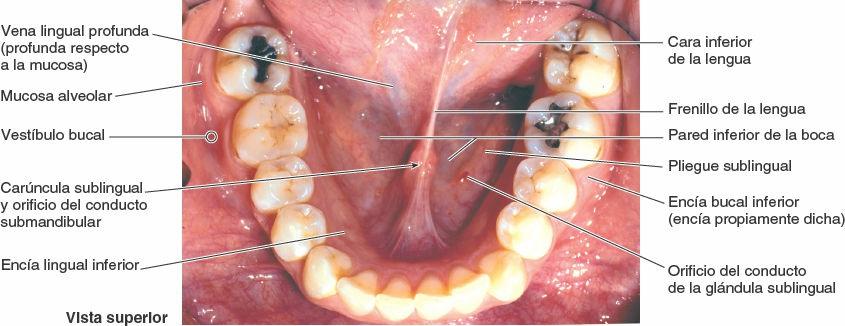

La cara inferior de la lengua está cubierta por una mucosa delgada y transparente (fig. 8-89). Esta cara conecta con la pared inferior de la boca mediante un repliegue medio denominado frenillo lingual, a pesar del cual puede moverse libremente la porción anterior de la lengua. A cada lado del frenillo, una vena lingual profunda es visible a través de la delgada mucosa. Existe una carúncula sublingual (papila) a cada lado de la base del frenillo lingual; en ella se encuentra el orificio del conducto submandibular, procedente de la glándula salival submandibular.